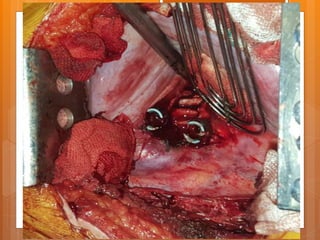

The segmental vessels

The parietal pleura

T12-L1 disc

ALL L1 T12

ALL

L1 T12